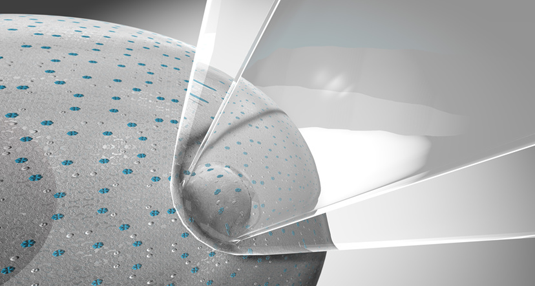

Patch-clamping provides a unique means of studying the electrophysiology of CLN3 in lysosomal vesicles. (Photo: sciencedisplay / fotolia.com)

Patch-clamping provides a unique means of studying the electrophysiology of CLN3 in lysosomal vesicles. (Photo: sciencedisplay / fotolia.com)

Patch-clamping provides a unique means of studying the electrophysiology of CLN3 in lysosomal vesicles. A micropipette is brought into contact with a vesicle and small patch of membrane is detached by applying gentle suction. The patch then covers the end of the pipette, forming a tight seal. By filling the pipette with various salt solutions and applying a voltage via a microelectrode, the researcher can measure ion transport through individual protein channels in the patch, establish whether a channel is active or inactive, and identify the types of ions that can pass through it. Grimm and his colleagues will use this method to determine the function of CLN3 in the lysosomal membrane. But they also hope to find substances that activate or deactivate the protein. “Trying to do this with patch clamping alone is akin to searching for the proverbial needle in a haystack. So we will first employ a screening procedure to identify likely candidates,” Grimm explains. “If we succeed in finding such a substance, we can investigate its effect on CLN3 in detail with the patch clamp.”